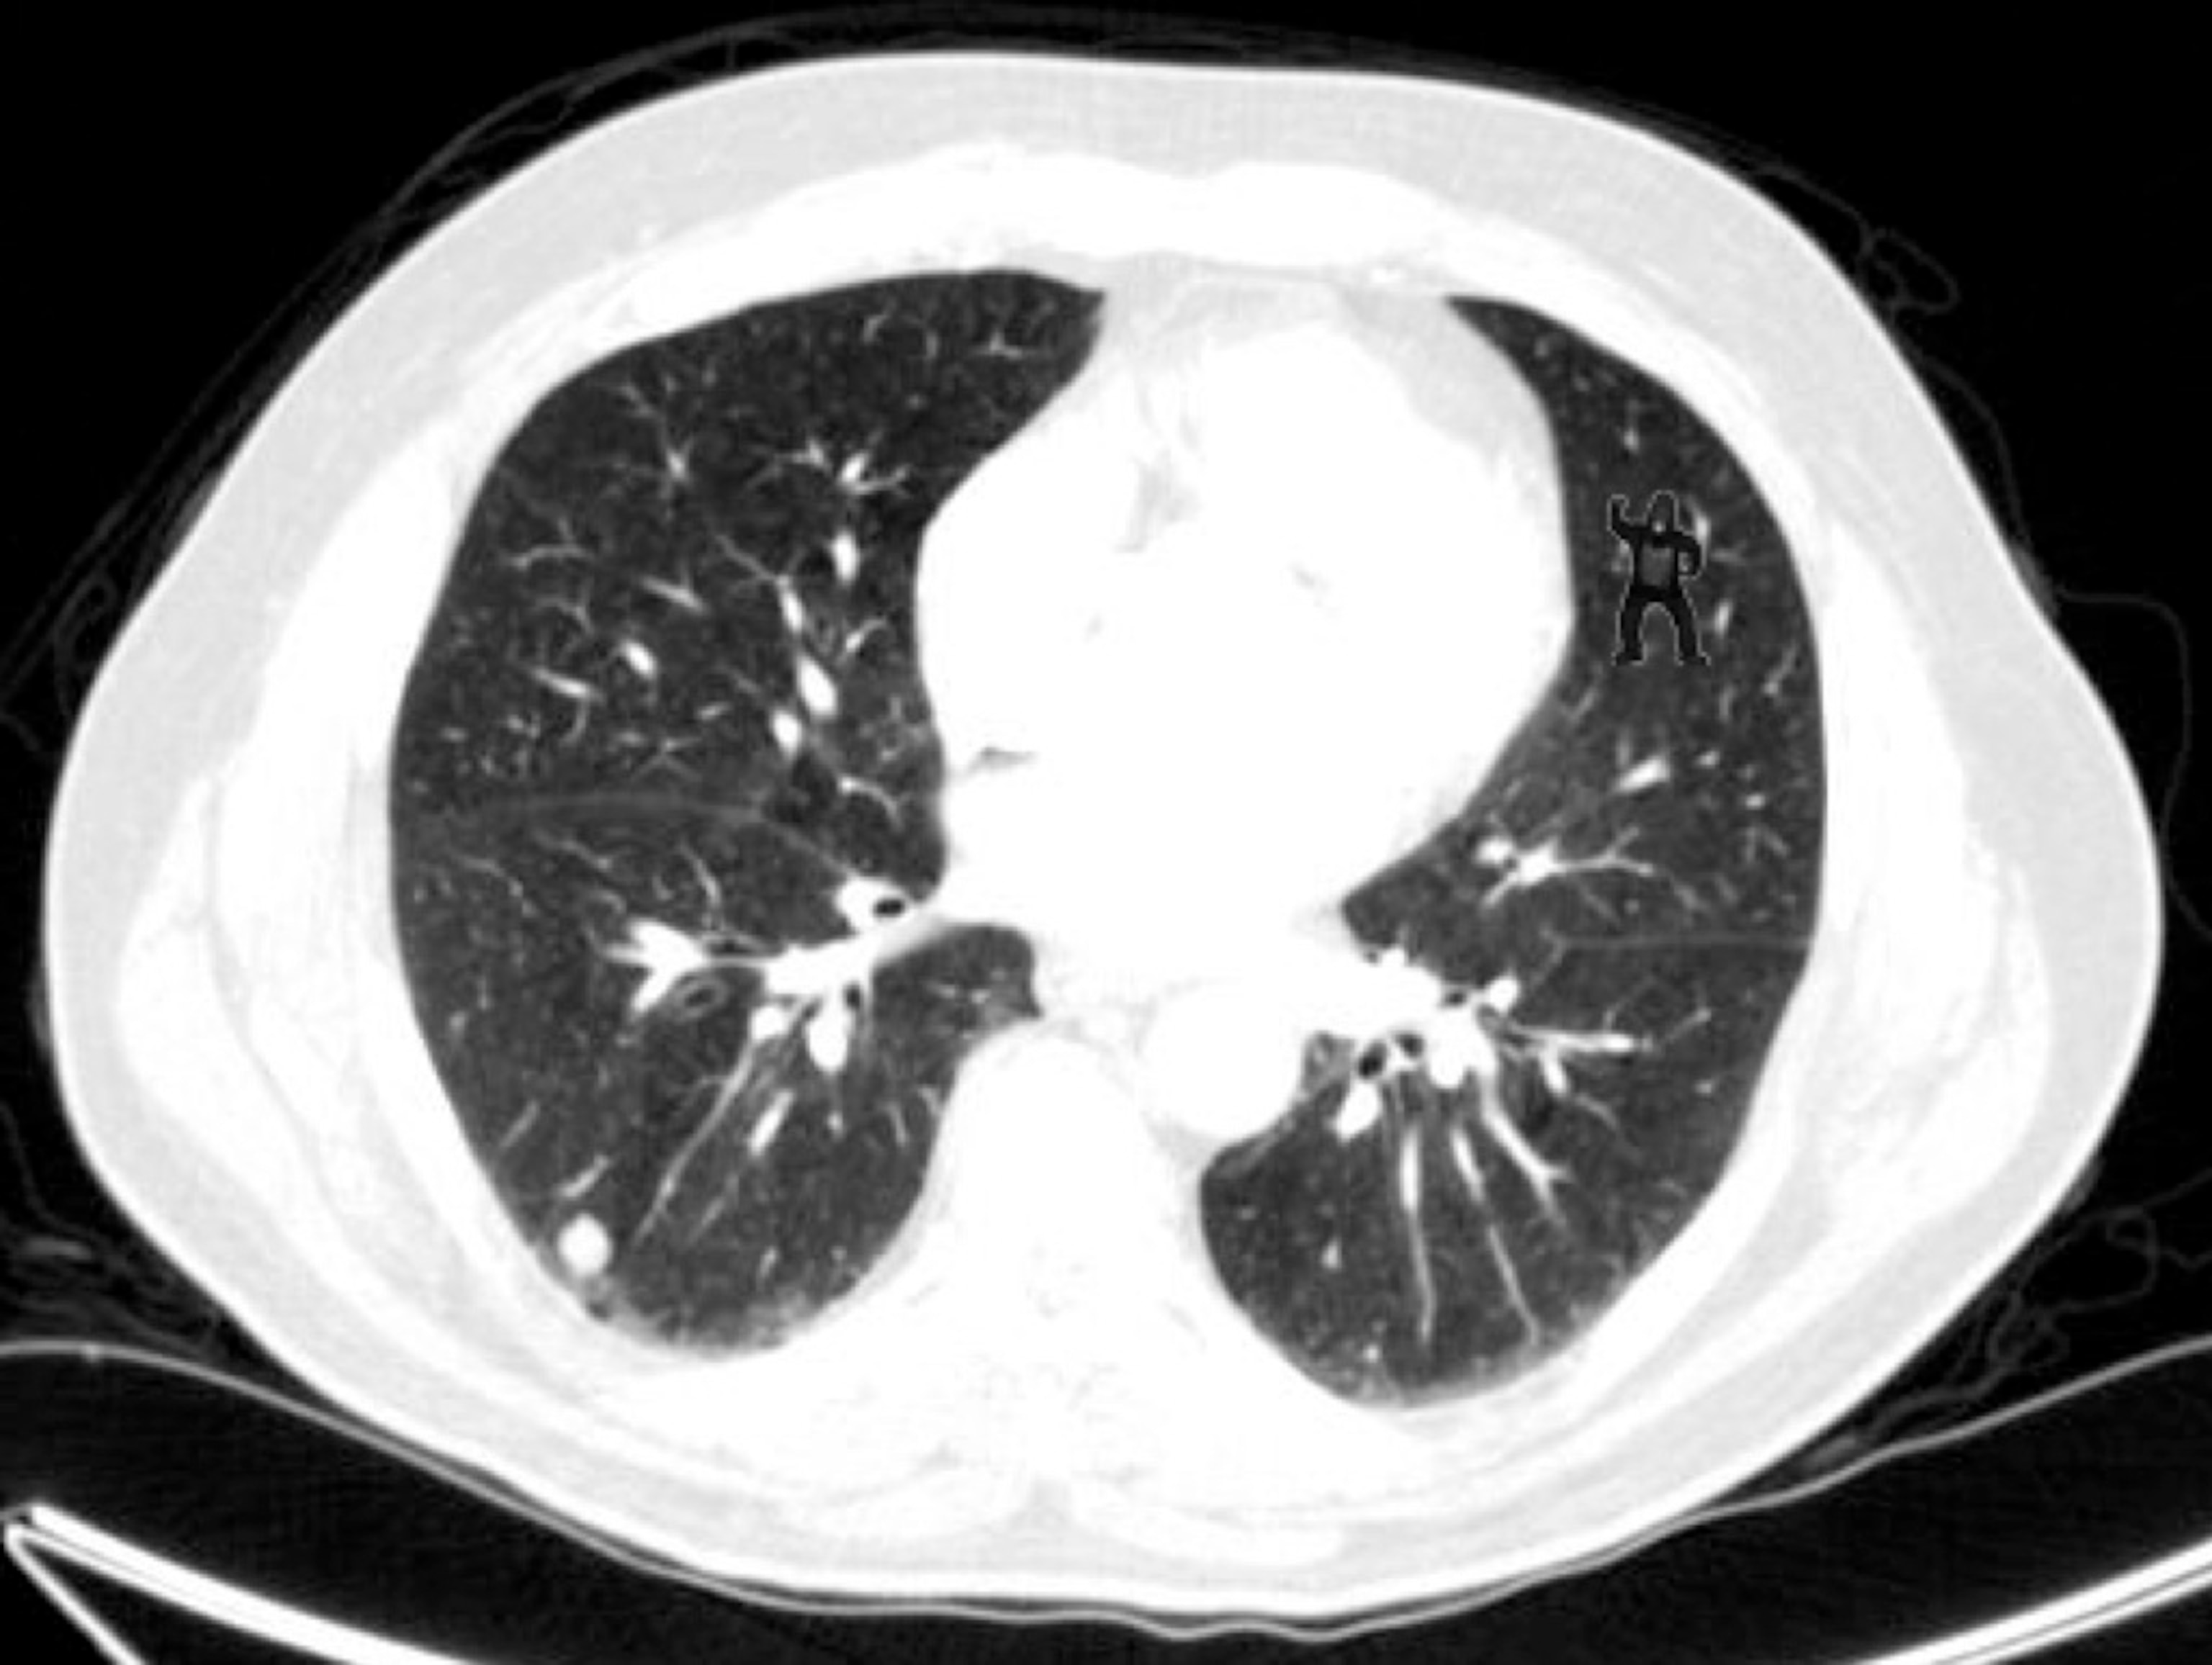

The picture above is an X-ray computed tomography (CT) scan of a human lung. Go ahead and take a few seconds to look at it carefully.

How long did it take you to spot the gorilla?

The image takes a starring role in a fun study in press at Psychological Science. Trafton Drew and colleagues at the Brigham and Women’s Hospital showed that when people focus on searching these images for bright white cancer nodules, they never notice the gorilla. More shocking, radiologists — who are trained to read CT scans — usually miss it, too.

In the new study, Drew asked 24 radiologists to do a typical lung cancer screening using the CT scans of five patients. This requires the radiologist to sit at a computer and look for small white blobs on hundreds of X-rays, each showing a slightly different slice of the patient’s lung. “It’s incredible to watch them do this,” Drew says. “They go through these things in under three minutes.”

The researchers didn’t do anything tricky to the images from the first four patients, which included on the order of 1,000 scans. But hidden in the stack of 239 images from the fifth patient, the researchers inserted 5 consecutive scans showing the cartoon gorilla. They were sneaky about it, too. On first appearance, the gorilla was 50 percent transparent. On the second it was 75 percent, and on the third fully visible. Then it faded back out on the last two scans.

Just 4 of the 24 radiologists reported seeing the gorilla. What’s more, the researchers had used eye-tracking technology to chart exactly where on the scans the participants had been looking. “The majority of them looked directly at the gorilla for extended periods of time. They just don’t see it,” he says.